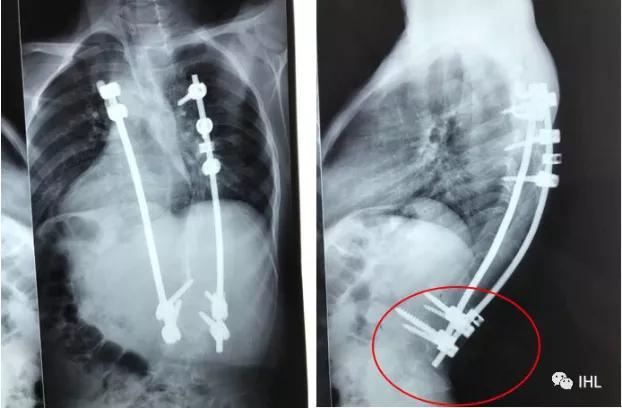

左边X片是Roye教授第一次看到孩子时的情况,而右边是Roye教授为孩子重新手术返修后的X片!

手术后孩子长高了近10公分,并且很快就可以下地行走了。